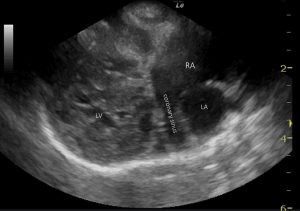

The right long axis four chamber view is markedly abnormal:

Abnormal findings include:

-RV wall hypertrophy (or pseudohypertrophy)

-RA dilation

-LV wall hypertrophy (or pseudohypertrophy)

-systolic anterior motion of the septal mitral valve leaflet

…..and, intriguingly, there is an abnormal vascular structure which is glimpsed running from the right atrium around the left atrium towards the left atrioventricular groove and then cranially.

This is the coronary sinus and it is abnormally dilated. This finding suggests that a persistent left cranial vena cava is present and is emptying into the right atrium (they sometimes go into the left).